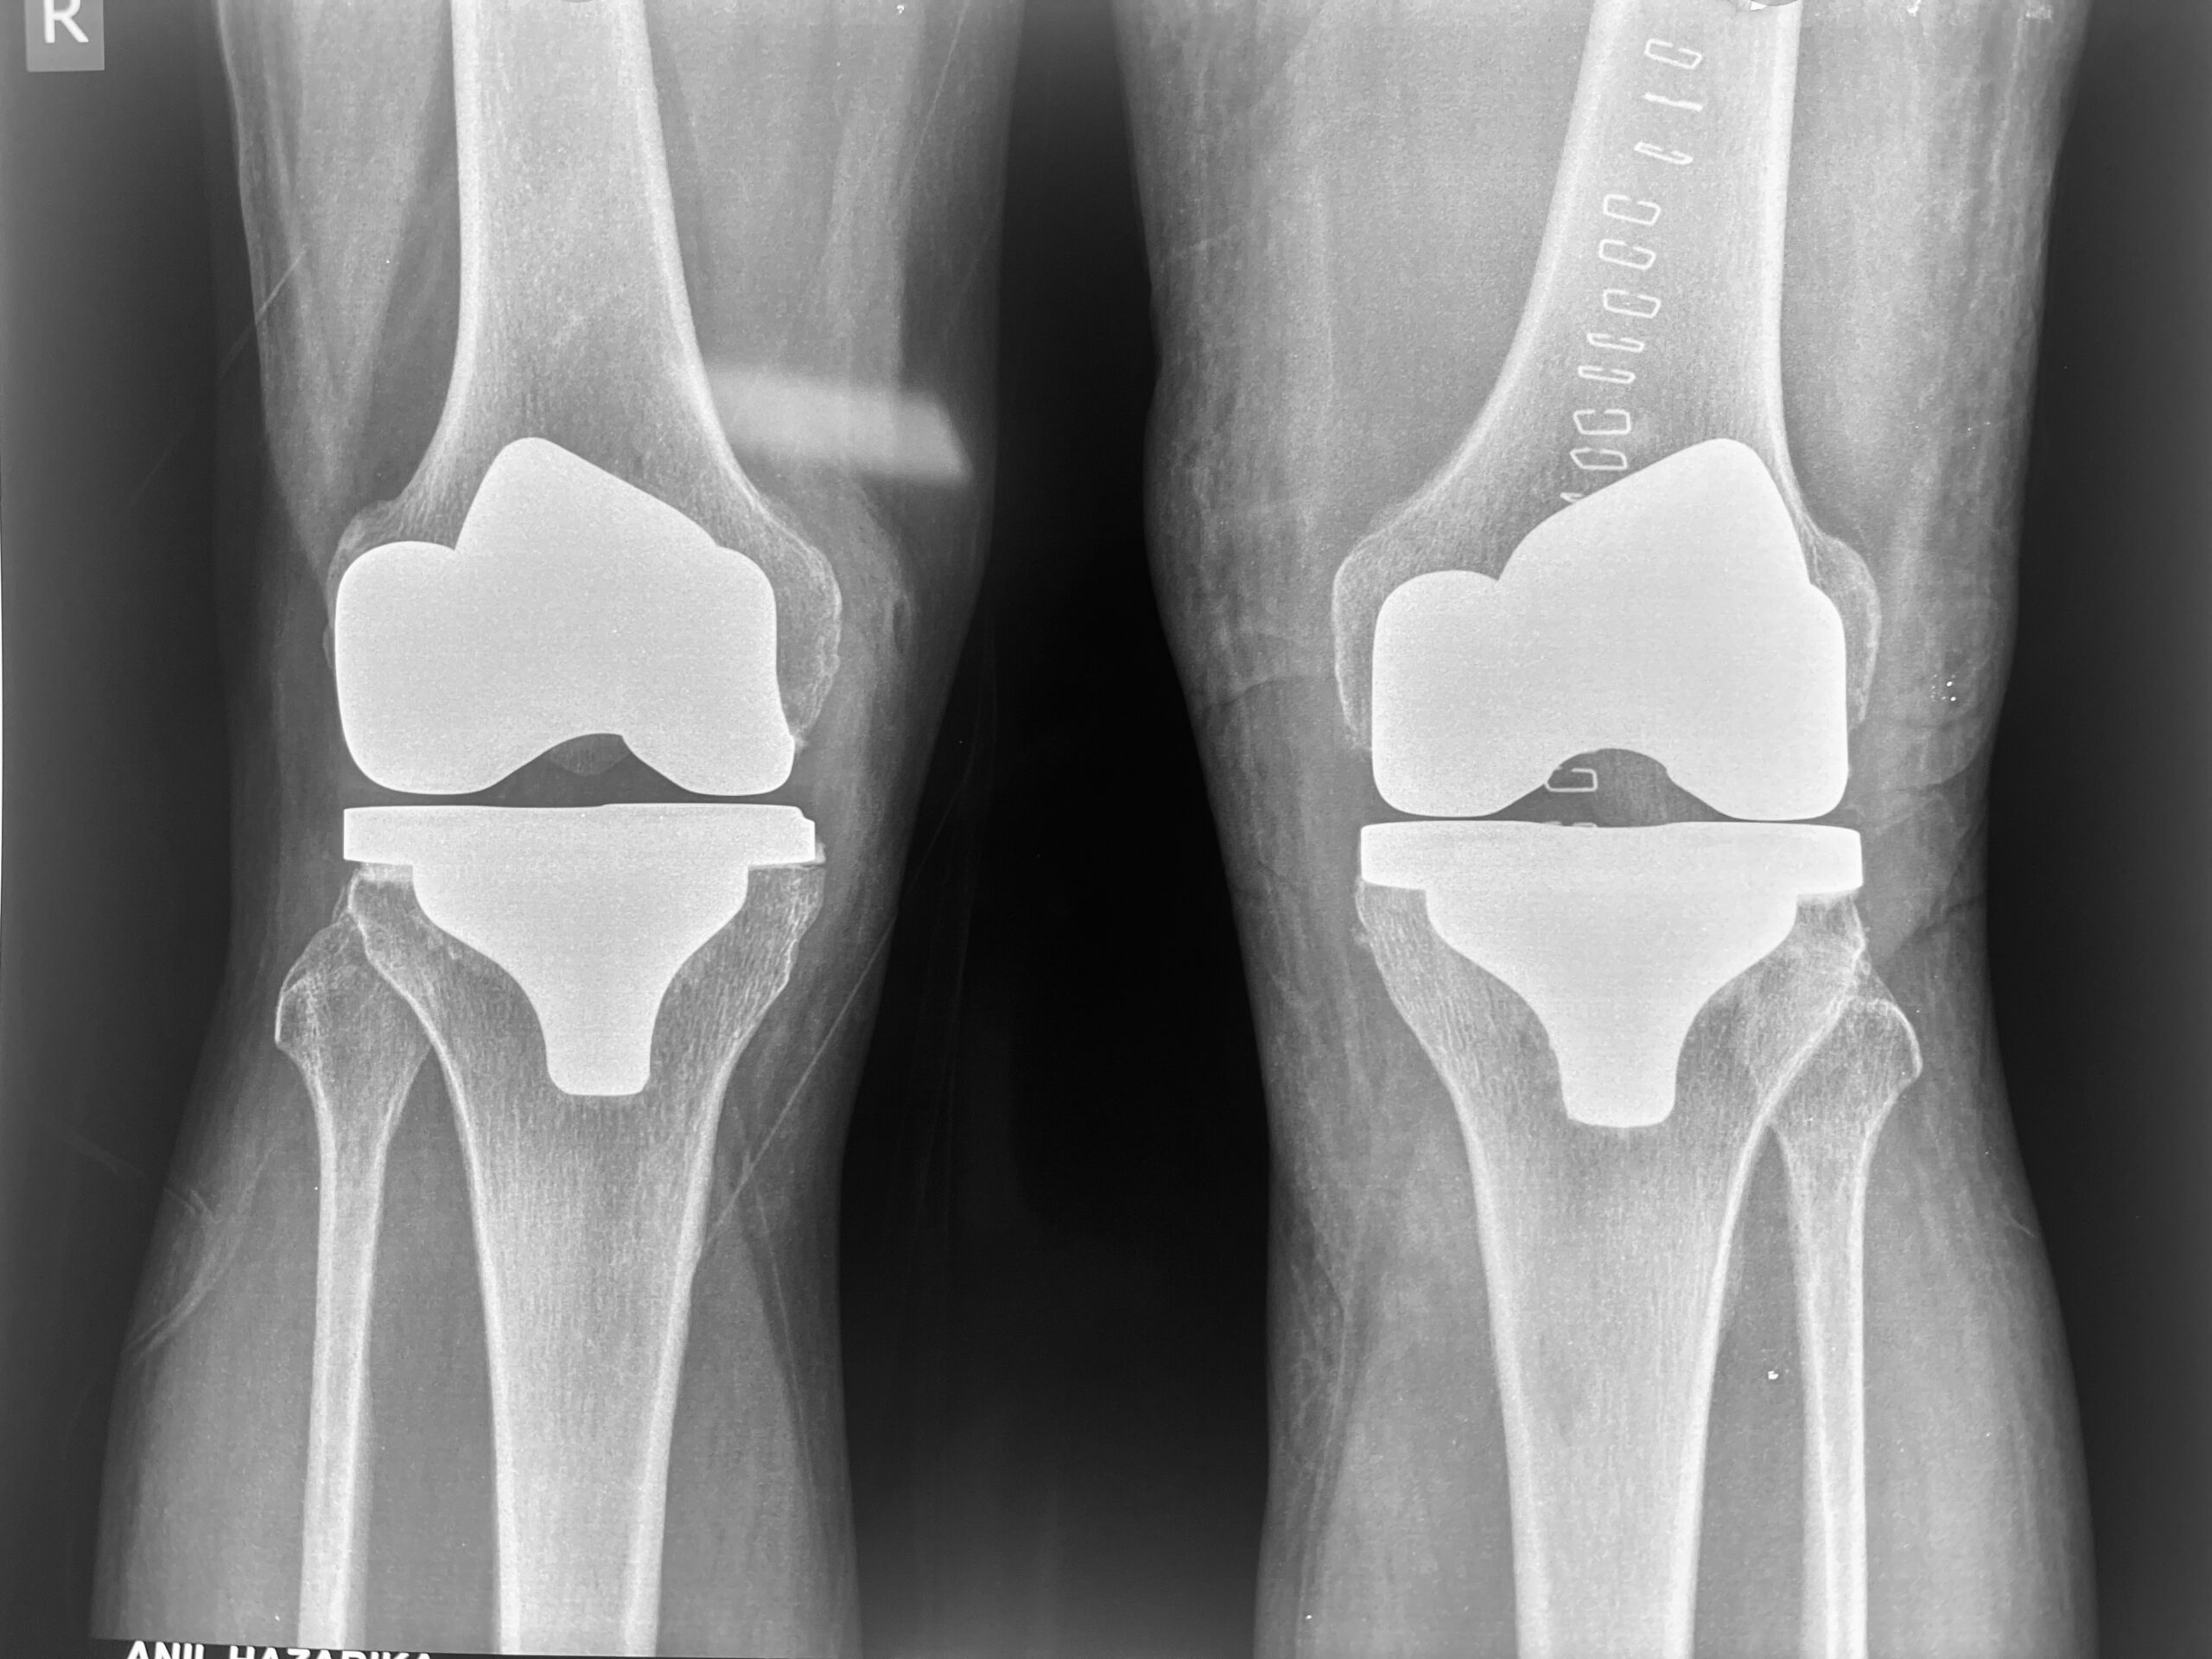

Knee Replacement Surgery

Recommended for severe arthritis with long-term pain and disability.

• Expertise in Knee Replacement and Arthroscopy